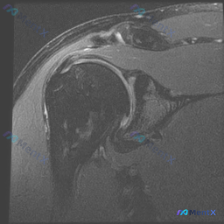

这个肩关节MRI病例的核心异常到底是什么?问题与报告矛盾点待理清

看到一个肩关节MRI病例资料,有个比较有意思的点:用户的问题是「What is the noticeable abnormality in this image?Labral pathology」(图像中明显的异常是什么?盂唇病变),但整理的影像分析报告核心发现是冈上肌腱全层撕裂。

先把报告里的关键影像学发现列一下:

- 冈上肌腱附着点信号显著增高,连续性受损,提示全层撕裂,断端回缩

- 肩峰下-三角肌下滑囊显著积液,有「液面交通征」

- 肩峰形态是钩状(Type III Acromion),肩峰下间隙小,和撞击相关

- 冈上肌肌腹有萎缩迹象,提示慢性损伤

- 骨骼和关节间隙没提明显问题